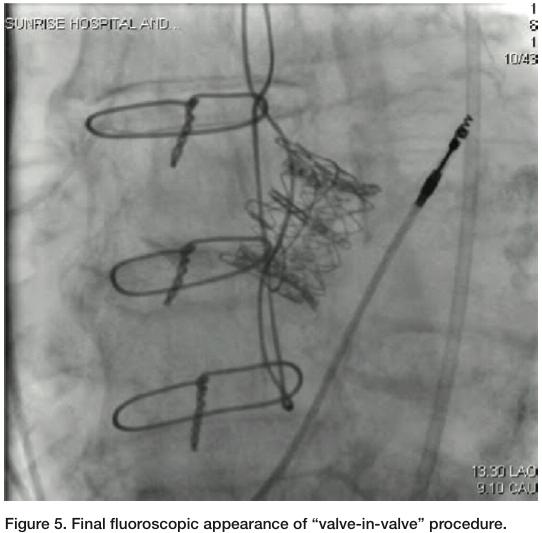

milliliter (mL) was taken out of the balloon on which the valve was mounted, because we were planning to place a 23 mm Sapien valve in the strut of a previously placed 21 mm prosthesis. The Sapien valve was then delivered through the 22 French delivery system and across the bioprosthetic aortic valve, utilizing the RetroFlex delivery system (Edwards Lifesciences). Care was made to position it so that the distal end of the Sapien valve was about 2 mm ventricular to the sewing ring of the previously placed aortic bioprosthesis (Figure 3). Under rapid pacing, the Sapien valve was deployed (Figures 4-5). Immediately post deployment, the aortic insufficiency was completely abolished, and peak velocity across the aortic valve was about 1 m/sec, with a peak velocity of about 3 m/sec at the beginning of the procedure.

The patient was recovered and extubated in the hybrid operating suite. Her hemodynamics were stable overnight. On post-operative day 1, she was ambulating, with improvement in dyspnea. An echo obtained twenty-four hours post procedurally was remarkable, with complete abolishment of the previously seen aortic regurgitation, and more surprisingly, near complete abolishment of the mitral regurgitation (Figures 6-7). LV size also appeared smaller and function had improved, with an ejection fraction of about 45%. The patient was uneventfully discharged from the hospital by post-operative day 4.